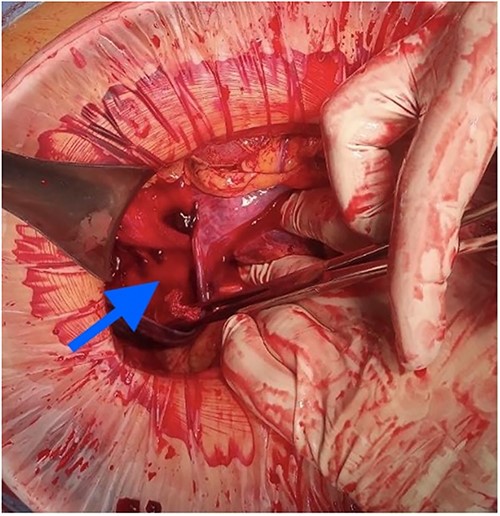

At laparotomy, it was apparent that a large hematoma had occupied the anterior aspect of the stomach causing extensive serosal stretch from fundus to pylorus (Fig. 4). Serous membrane under hematoma was ruptured and about 500 ml of hemorrhagic liquid with clots was detected in the peritoneal cavity. Serous membrane rupture was widened, evacuated blood clots and revealed small branch of left gastric artery as origin of bleeding (Fig. 5). Suture ligation of artery was performed. Surgery finished by drainage of abdominal cavity, cavity of hematoma with serous membrane suturing, and microjejunostomy for post-operative nutritional support.

The etiology of the hematoma was not proven by pathological findings. He was admitted to the general surgical ward after surgery and discharged on the eighth post-operative day. Microjejunostomy tube was removed on the 30th post-operative day without complications.